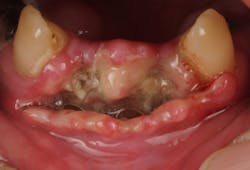

Late complications of bone augmentation are now recognized more frequently and include late resorption, foreign body reaction (figures 2a–2b), late breakdown of grafted sites (figures 3a–3e), lack of keratinized tissue and poor esthetics, as well as implant failure. While all bone augmentation procedures result in some degree of bone remodeling and resorption, significant late graft resorption can jeopardize the supporting bone around an already integrated implant, resulting in implant dehiscence, peri-implant disease, and late implant failure (figures 4a–4c). The degree of resorption depends on three important factors: alveolar defect configuration, patient factors, and the technique and grafting materials chosen.3

Figures 3a–3e: Socket preservation was performed at the site of the left mandibular second molar after extraction, using a biomaterial two years prior to implant placement. Six years after implant placement, sequestration of the biomaterial is seen, resulting in peri-implant infection and failure of the implant.